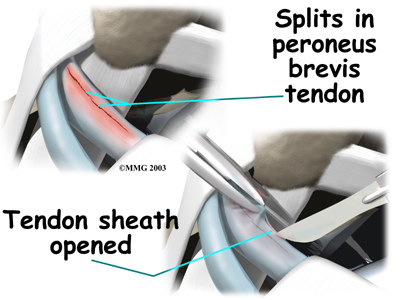

Over time, the tendon thickens as scar tissue tries to repair the damaged tendon. The area of tendonosis in the tendon is weaker than normal tendon. The weakened, degenerative tendon may tear. This usually causes a lengthwise in the peroneal tendons rather than a rupture. These splits or tears are most common in the peroneus brevis tendon, probably because it lies in front of the peroneus longus. It is more vulnerable to friction because it rubs against the groove in the fibula bone.

Tendon Repair

Tendonosis may require repair if a preoneal tendon is split down its length. This type of tear mainly affects the peroneus brevis. The surgeon fixes this problem by first around the tendons. If the split is smaller than one-third the width of the tendon, the torn portion may simply be removed. Larger splits are sutured along the length of the tendon. The tendon sheath is , and the skin is closed with sutures.